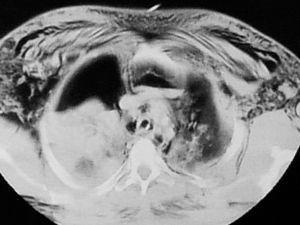

Fig. 4. Tomografía computarizada de tórax del caso 10, que presentaba una lesión bronquial traumática. Se trasladó al paciente desde un hospital secundario y se le trató quirúrgicamente sin resección pulmonar. En este caso el tratamiento inicial se intentó sin reparación bronquial con medidas conservadoras, pero el aumento del enfisema subcutáneo, el neumotórax traumático y la atelectasia de pulmón derecho casi completa obligaron a la realización de reparación plástica bronquial.